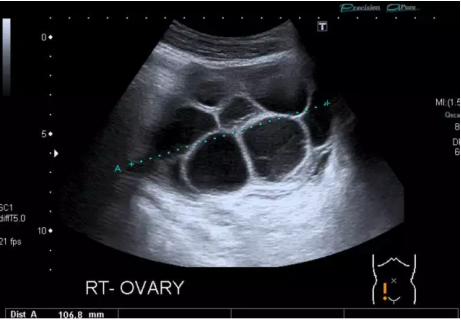

取卵是試管嬰兒周期内最重要的環節,卵子質量關乎着成功率,所以大家對此都非常重視。但在取卵後,很多人都出現一定的不适,其中就包括腹水。取卵後腹水的主要原因是卵泡在排卵過程中過度發育,藥物過度刺激卵巢造成的。很多女性取卵後都會有腹水的情況,這一點不可避免,特别是那些高齡或者卵巢功能不好的女性,這種情況可能是取卵及促排卵藥物對卵巢造成的卵巢過度刺激綜合征,從而引起了腹水、腹痛等并發症。當然每個人的身體體質都不一樣,所以出現的不良反應也因人而異。